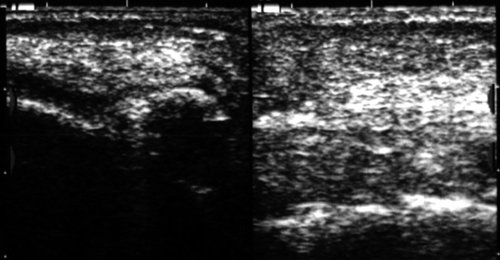

Рис. 11. Сиаладенит правой поднижнечелюстной железы.

Применение эхографии при внеорганных воспалительных процессах на лице и шее позволяет различить гнойное (абсцесс, флегмона) и негнойное (ин фильтрат) поражение мягких тканей, а при выявлении гнойного поражения точно локализовать скопления гноя (рис. 12-14).

Рис. 12. Инфильтрат левой щечной области.